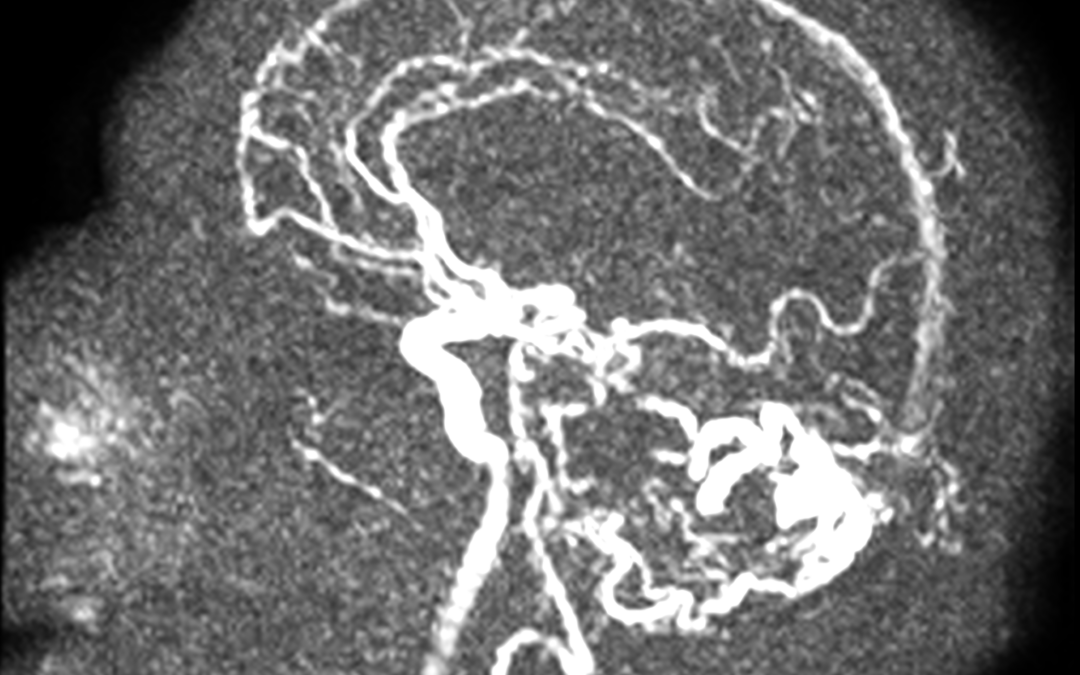

Estudio de inestabilidad, se activó código ictus sin identificar oclusión de gran vaso.Enlace al caso de neurorradiología.